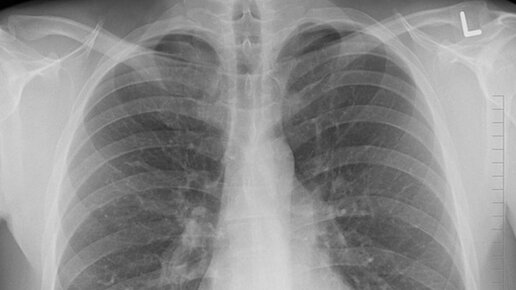

Пневмония: как определить воспаление легких, почему оно смертельно опасна и когда нужно срочно вызывать скорую

Как проходит пневмония у человека, какие первые «звоночки». Знаменитости заболели пневмонией. Заболевание «пневмония» - 4-ое в списке по смертности. Причинами возникновения воспаления нижних дыхательных путей могут быть: - грибковые инфекции; - вирусные инфекции; - неинфекционные факторы, например, травмы грудной клетки, токсические вещества и другие. У людей среднего возраста острая форма пневмонии встречается в 10-14 случаях на 1000 зараженных людей. У тех, кто старше 50-ти лет, острая форма уже в 17-ти случаях из 1000 человек - зараженных...